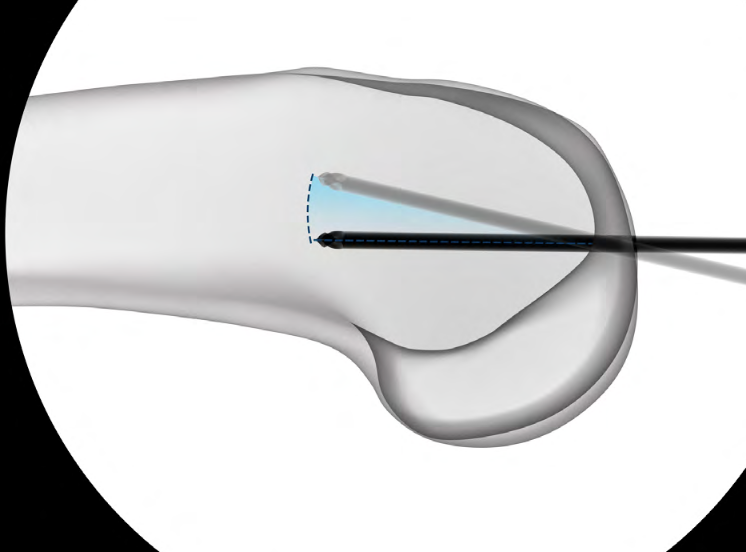

Entry point

- medial parapatella approach

- entry above notch slightly medial

- slightly anterior and lateral to femoral attachment of PCL

- central in AP and lateral of the distal fragment

- awl / 3.2 mm guide wire

- ream for enlarged end of retrograde nail